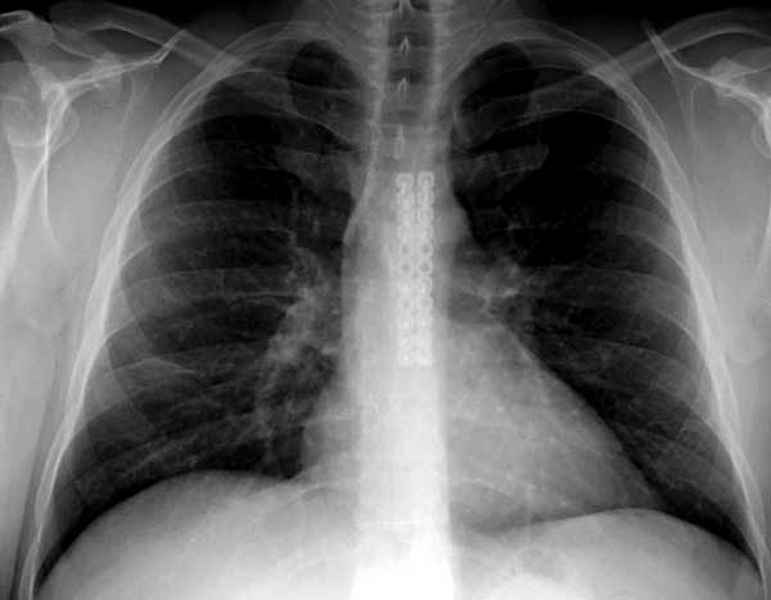

Юра, интересно, насколько такой остеосинтез контролирует степень репозиции, а то у меня имеются снимки девочки 11 лет, направленной ко мне на консультацию из одной из республик бывшего союза.

После торакальной операции, по-видимому, сильно натянули проволоку, и в результате получился захлест отломков в друг друга.

Оперировавший хирург предлагает подождать, а родителей беспокоит проблема прогрессирующей ассиметрии лица, как при кривошее.

С такими продольными несращениями мне не приходилось иметь дело, поэтому направил в один из центральных институтов детской ортопедии России.